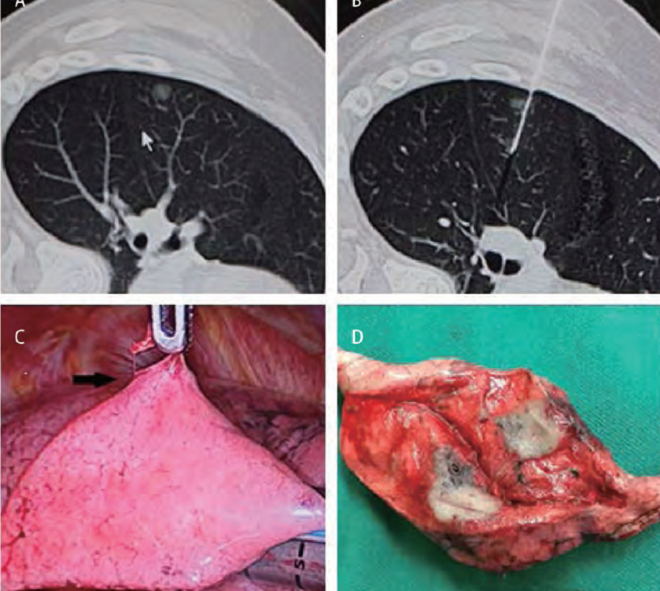

肺部結節是指肺部出現的圓形或不規則形狀的異常組織增生,通常通過醫學影像技術如X光、CT掃描等檢查發現,肺部結節可能是良性的,也可能是惡性的,其形成原因多種多樣,包括感染、炎癥、良性腫瘤和肺癌等。

1、張先生是一位45歲的白領,因工作繁忙、生活壓力大,被診斷為肺部結節,在嘗試多種治療方法后,他決定嘗試食用三七,經過半年的堅持,他的肺部結節竟然消失了。

2、李女士是一位50歲的家庭主婦,因長期接觸油煙和空氣污染,患上了肺部結節,在醫生的建議下,她開始食用三七并調整生活習慣,一段時間后,她的肺部結節也成功消除。